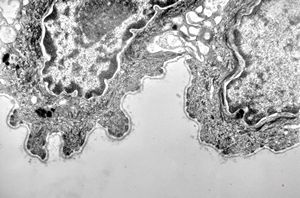

M, 48y. | multiplication of dermal perivascular basement membranes (unclassified myopathy)

F, 48y. | lupus erythematodes … multiplicated vascular basement membrane

F, 48y. | lupus erythematodes … multiplicated vascular basement membrane

F, 48y. | lupus erythematodes … multiplicated vascular basement membrane